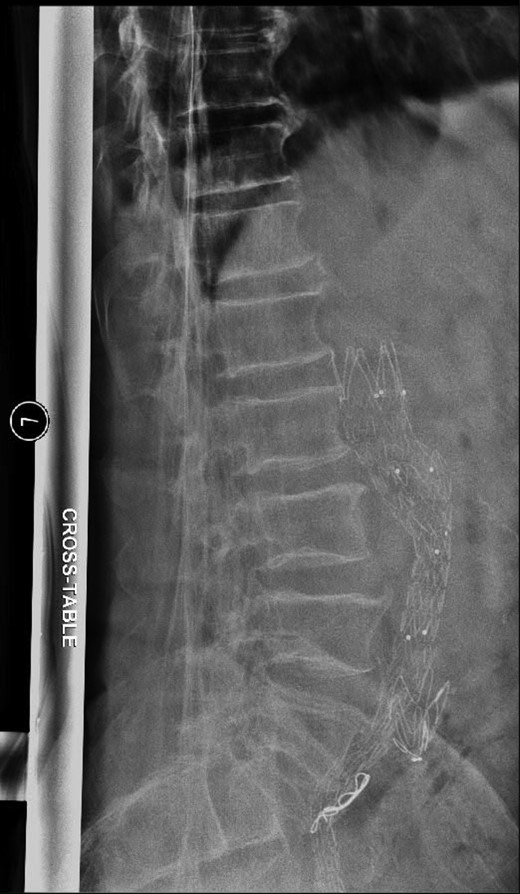

AP radiograph of the lumbar spine demonstrating the aortouniiliac EVAR with coil embolization of the right CIA.

Lateral radiograph of the lumbar spine demonstrating the aortouniiliac EVAR with coil embolization of the right CIA.